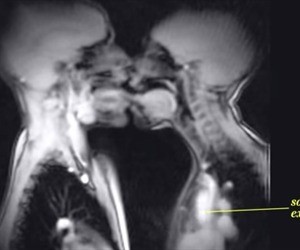

Dentro del video se puede ver el funcionamiento del cuerpo cuando se da un beso, no sólo los movimientos de la boca sino la aceleración del ritmo cardiaco; también se puede ver el funcionamiento del cerebro y cómo se ve un embarazo.